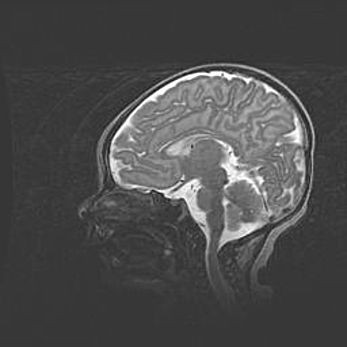

Ниже представлена  галерея МРТ снимков, полученных с применением LMT неонатальных матричных РЧ катушек. Также каждая группа МРТ снимков сопровождается информацией о пациенте (диагноз, возраст, вес, пол, срок гестации) и краткой сопроводительной расшифровкой диагноза.

Аномалия Денди-Уокера. Признаки гипоплазии мозолистого тела.

Возраст: 5 месяцев 3 дня

Вес: 5550 г

Пол: мужской

Окружность головы: 39 см

Срок гестации: 40 недель

Аномалия Денди-Уокера – это порок развития головного мозга, для которого характерна триада симптомов: гипотрофия или аплазия червя мозжечка и/или полушарий мозжечка, расширение четвёртого желудочка с формированием ликворной кисты задней черепной ямки, гипертензионная гидроцефалия различной степени.

Гипоплазия мозолистого тела относится к дефектам внутриутробного этапа развития мозговой ткани, возникающим в процессе закладки структур головного мозга, что происходит на начальных этапах развития эмбриона.